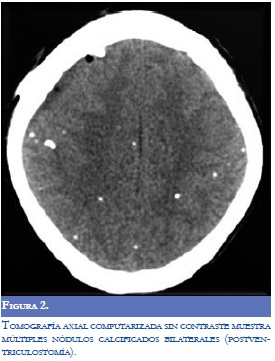

Los laboratorios realizados (hemograma, electrólitos, proteína C-reactiva, VDRL y VIH) fueron normales. Se realizó punción lumbar pero no se obtuvo retorno de líquido cefalorraquídeo (LCR) por bloqueo del espacio subaracnoideo. El LCR se obtuvo por medio de ventriculostomía externa y su análisis mostró hipoproteinorraquia; posteriormente se realizó derivación ventriculoperitoneal y se realizó un segundo análisis de LCR (Tabla 1). La reacción en cadena de polimerasa para tuberculosis fue negativa en LCR (otros análisis se encontraron normales). Los niveles de inmunoglobulina G en sangre fueron positivos para cisticerco (Índice IgG de 4,57; V.R. menor de 0,35). La primera resonancia magnética del cerebro realizada al ingreso al servicio de urgencias mostró marcada hidrocefalia (Figura 1). Después de la ventriculostomía externa, y la colocación de la derivación ventrículoperitoneal, la tomografía axial computarizada del cerebro (TAC) mostró múltiples nódulos calcificados sugestivos de NCC sin edema perilesional (Figura 2). La RM de la médula espinal reveló paquimeningitis generalizada, realce meníngeo y lesiones nodulares sugestivas de NC subaracnoidea (Figura 3). Otros estudios imaginológicos como TAC toracoabdominal con contraste y gamagrafía ósea se encontraron dentro de los límites normales. La biopsia meníngea realizada reveló la presencia de células fibrosas monomórficas rodeadas por tejido colagenosos, sin parásitos, compatible con inflamación crónica o hidrocefalia crónica.

El estadio final se desarrolla cuando los quistes evolucionan a la fase calcificada, donde se convierten en nódulos calcificados e inertes. Esta fase es la más frecuente y el diagnóstico se realiza principalmente mediante la TAC simple, que muestra múltiples lesiones pequeñas hiperdensas sin edema perilesional. Aunque en la RM estas lesiones inactivas pueden realzar con gadolinio, en esta etapa la TAC adquiere más importancia que la RM debido a su sensibilidad para identificar calcificaciones (Figuras 2 y 3).